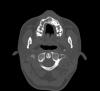

persona Опубликовано 12 октября, 2008 Автор Поделиться Опубликовано 12 октября, 2008 (изменено) Кроме того, проходил КТ. Выкладываю несколько срезов в области клыка. Изменено 12 октября, 2008 пользователем persona Ссылка на комментарий

Force Опубликовано 12 октября, 2008 Поделиться Опубликовано 12 октября, 2008 Кроме того, проходил КТ. Выкладываю несколько срезов в области клыка. А кто из врачей делал Вам трг перед планированием с расчетом? а расчет моделей делали? Ссылка на комментарий

Премоляр Опубликовано 14 октября, 2008 Поделиться Опубликовано 14 октября, 2008 Хм, честно говоря, у меня тоже небольшие сомнения вызывала возможность отцентровки при таком лечении.Т.е. вы за вариант лечения с имплантом? Но в этом случае точно придется удалять ретинированный клык, а при 2-ом плане лечения его можно было бы не трогать.Поставить в зубную дугу ретенир.клык будет очень очень травматично и сложно.И оставлять "просто так" клык тоже нельзя-т.к. со временем вокруг клыка может образоваться киста.(а может и нет...). Возможно целесообразнее удалить нижнюю 4ку справа(коррекция центра) и выравнивание зубов на вер.чел+последующая реставрация 4 ки сверху справа. И еще-сделать КТ для определения точной локализации ретенир.зуба(решения вопроса о его дальнейшей судьбе) Ссылка на комментарий

persona Опубликовано 14 октября, 2008 Автор Поделиться Опубликовано 14 октября, 2008 Поставить в зубную дугу ретенир.клык будет очень очень травматично и сложно.И оставлять "просто так" клык тоже нельзя-т.к. со временем вокруг клыка может образоваться киста.(а может и нет...). Возможно целесообразнее удалить нижнюю 4ку справа(коррекция центра) и выравнивание зубов на вер.чел+последующая реставрация 4 ки сверху справа. И еще-сделать КТ для определения точной локализации ретенир.зуба(решения вопроса о его дальнейшей судьбе)Спасибо большое за ответ. Только я не совсем понял насчет 4-ок. Может имелись в виду не правые, а левые 4-ки? Если так, то это получится в точности 2-ой вариант из тех, что я написал в первом посте. Ретинированный клык все врачи кроме одного рекомендуют не трогать, т.к. пока не беспокоит и корней других зубов вроде не задевает. КТ я сделал. Несколько срезов выложены во 2-ом посте. Если надо, могу выложить еще, но они все горизонтальные. Также есть еще снимок с 3-мерным изображением, но не думаю, что там лучше видно. Ссылка на комментарий